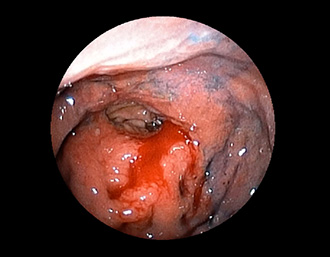

症例2:胃がん(66才男性)

術後胃(B-Ⅱope magen:十二指腸潰瘍手術)。吻合部の後壁側、軽度陥凹の白色病変を認める。生検:Group 5、Signent-ring cell carcinoma(印環細胞癌)と診断[早期胃癌]。高次医療機関へ紹介となり、残胃全摘術(リンパ節郭清)を行いました。

通常画像